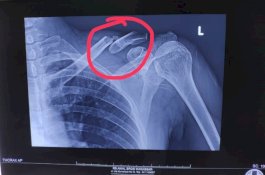

Selamat dari Tabrakan, Dosen STIBA Patah Tulang saat Menuju Masjid untuk Khotbah Jumat